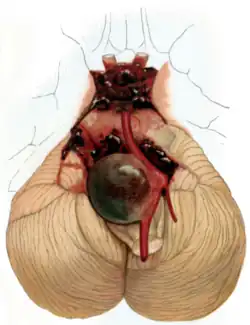

Aneurysma mozkových cév neboli mozková výduť je onemocnění cév, kdy se v oslabeném místě céva vychlipuje a vytváří abnormální tvar. Výduť pak může prasknout, což vede ke krvácení a vážnému ohrožení života. Onemocnění se obtížně diagnostikuje a většina lidí o něm neví.[1]

Praskne-li céva, provází pacienta velmi silná bolest, pacient může ztratit vědomí, může dostat epileptické křeče, zvracet, může mít strnutí šíje, nesnášenlivost světla a hluku.[1] Metodu léčby určuje tým tvořený neurochirurgy a radiology. Operovat by se mělo nejlépe do tří dnů od začátku krvácení. Aneurysmata se obvykle řeší zasvorkováním při neurochirurgické operaci nebo zavedením speciální spirálky, která dá vytvořit sraženině a krev přestane vytékat, přímo do výdutě. Děje se tak při radiologickém zákroku. [2]